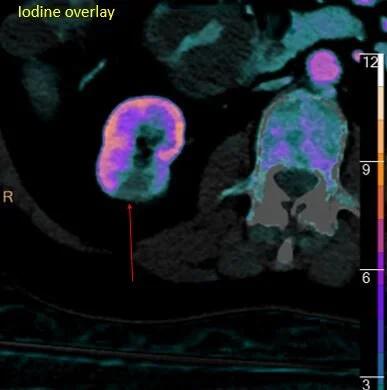

Oblique axial iodine overlay shows inflamed loop of terminal ileum (red arrow). Note upstream dilatation.

Hypodensity right kidney lower pole. Could be pyelonephritis or infarct.

Absent iodine uptake. Still could be pyelonephritis or infarct.